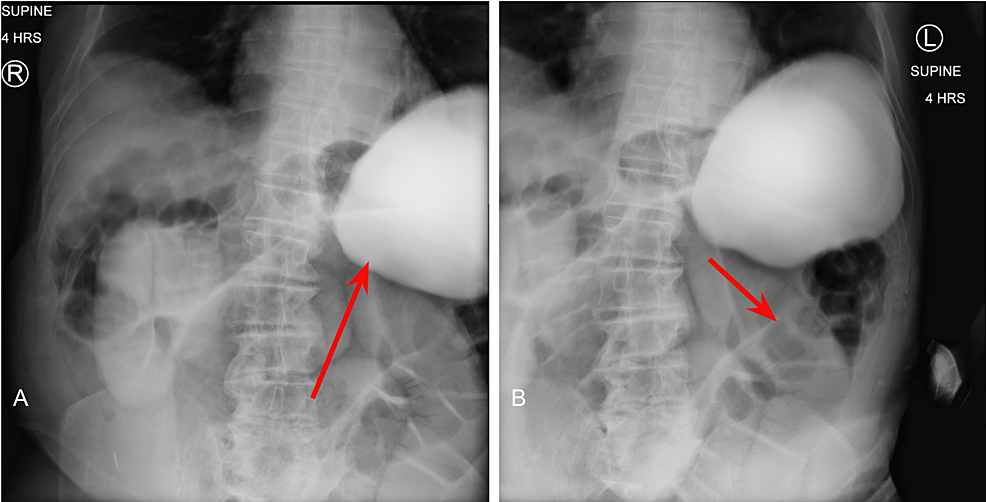

His POI was thought to have resolved after having one bowel movement approximately one week into his postoperative recovery; however, the following day, he presented with nausea, vomiting, tachycardia, and abdominal distension. A kidney, ureter, and bladder (KUB) plain radiograph was ordered, and re-demonstrated signs of ileus without perforation (Figure 4). Given the patient’s previous history of abdominal surgeries, we suspected another bowel obstruction, secondary to abdominal adhesions, as the cause of his prolonged ileus. We also considered a failed anastomosis. We discussed the possibility of performing another operation to identify and lyse any remaining adhesions, along with a possible correction of the resections and anastomoses we performed with end ileostomy and colostomy as traditionally indicated.